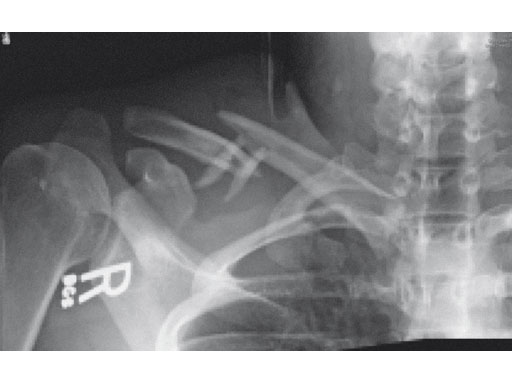

A 22-year-old man sustained an open clavicle fracture after a motorcycle injury.

Fig 1ab Preoperative x-rays.